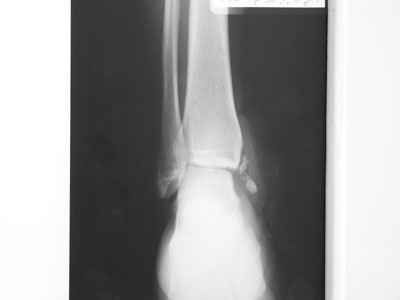

Совершенно верно был такой Пациент парень 29 лет. Только не 2 года а 4 года назад. Лечение растянулось на 2 этапа. На момент сообщения наложил окончатую гипсовую повязку, мазевые повязки, грануляции, закрыл свободной кожной пластикой. Через 2 месяца рана закрылась рубцом, гипс снял отправил на ЛФК. В течение года появлялся дважды - все ОК, нестабильности в суставе не было. Пациент работник УВД - его даже не комисовали. Обратился через 2 года после повторной травмы (опять мотоцикл) - открылся свищ в области медиальной лодыжки. Проведена операция - санация, рубец иссечен, пластика суральным лоскутом - состоятельная. Аппарат Илизарова на 2 месяца. Аппарат демонтировали опять ЛФК - Нестабильности в суставе нет, до сих пор трудится в органах... Опять подумывает о покупке мотоцикла.

К сожалению снимки нашел только после пластики. Р-гр где-то утерял посмотрю не работе.